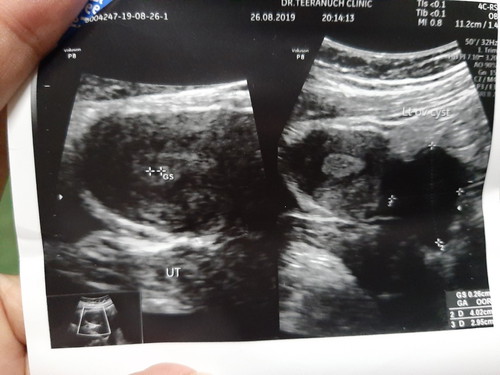

หมอแจ้งอาจเป็นถุงตั้งครรภ์ ??

ตรวจ2ขีดจะเจอเฉพาะตอนเช้า ตอนเย็นหรือบ่ายจะไม่ขึ้น2ขีด คัดเต้า มีปุ่มที่ลานนมขึ้นมา เวียนหัว แบบนี้จะใช่มั้ยคะแม่ๆ ยังไม่ถึงเดือนเลยค่ะ แต่หมอบอกถุงหนามากค่ะถ้าใช่ก็จะอ่อนมากๆ ให้รอลุ้นอีก2อาทิตย์ กังวลมากเลยค่ะ

อาจจะยังท้องอ่อนๆอยู่ค่ะ ที่ตรวจเช้าเจอเพราะฮอร์โมนมีเยอะสุดช่วงเช้า บ่ายเย็นฮอร์โมนมีน้อยไม่เจอถือว่าไม่แปลกค่ะ ท้องชัวร์ค่ะ แต่อายุครรภ์ยังน้อยอยู่